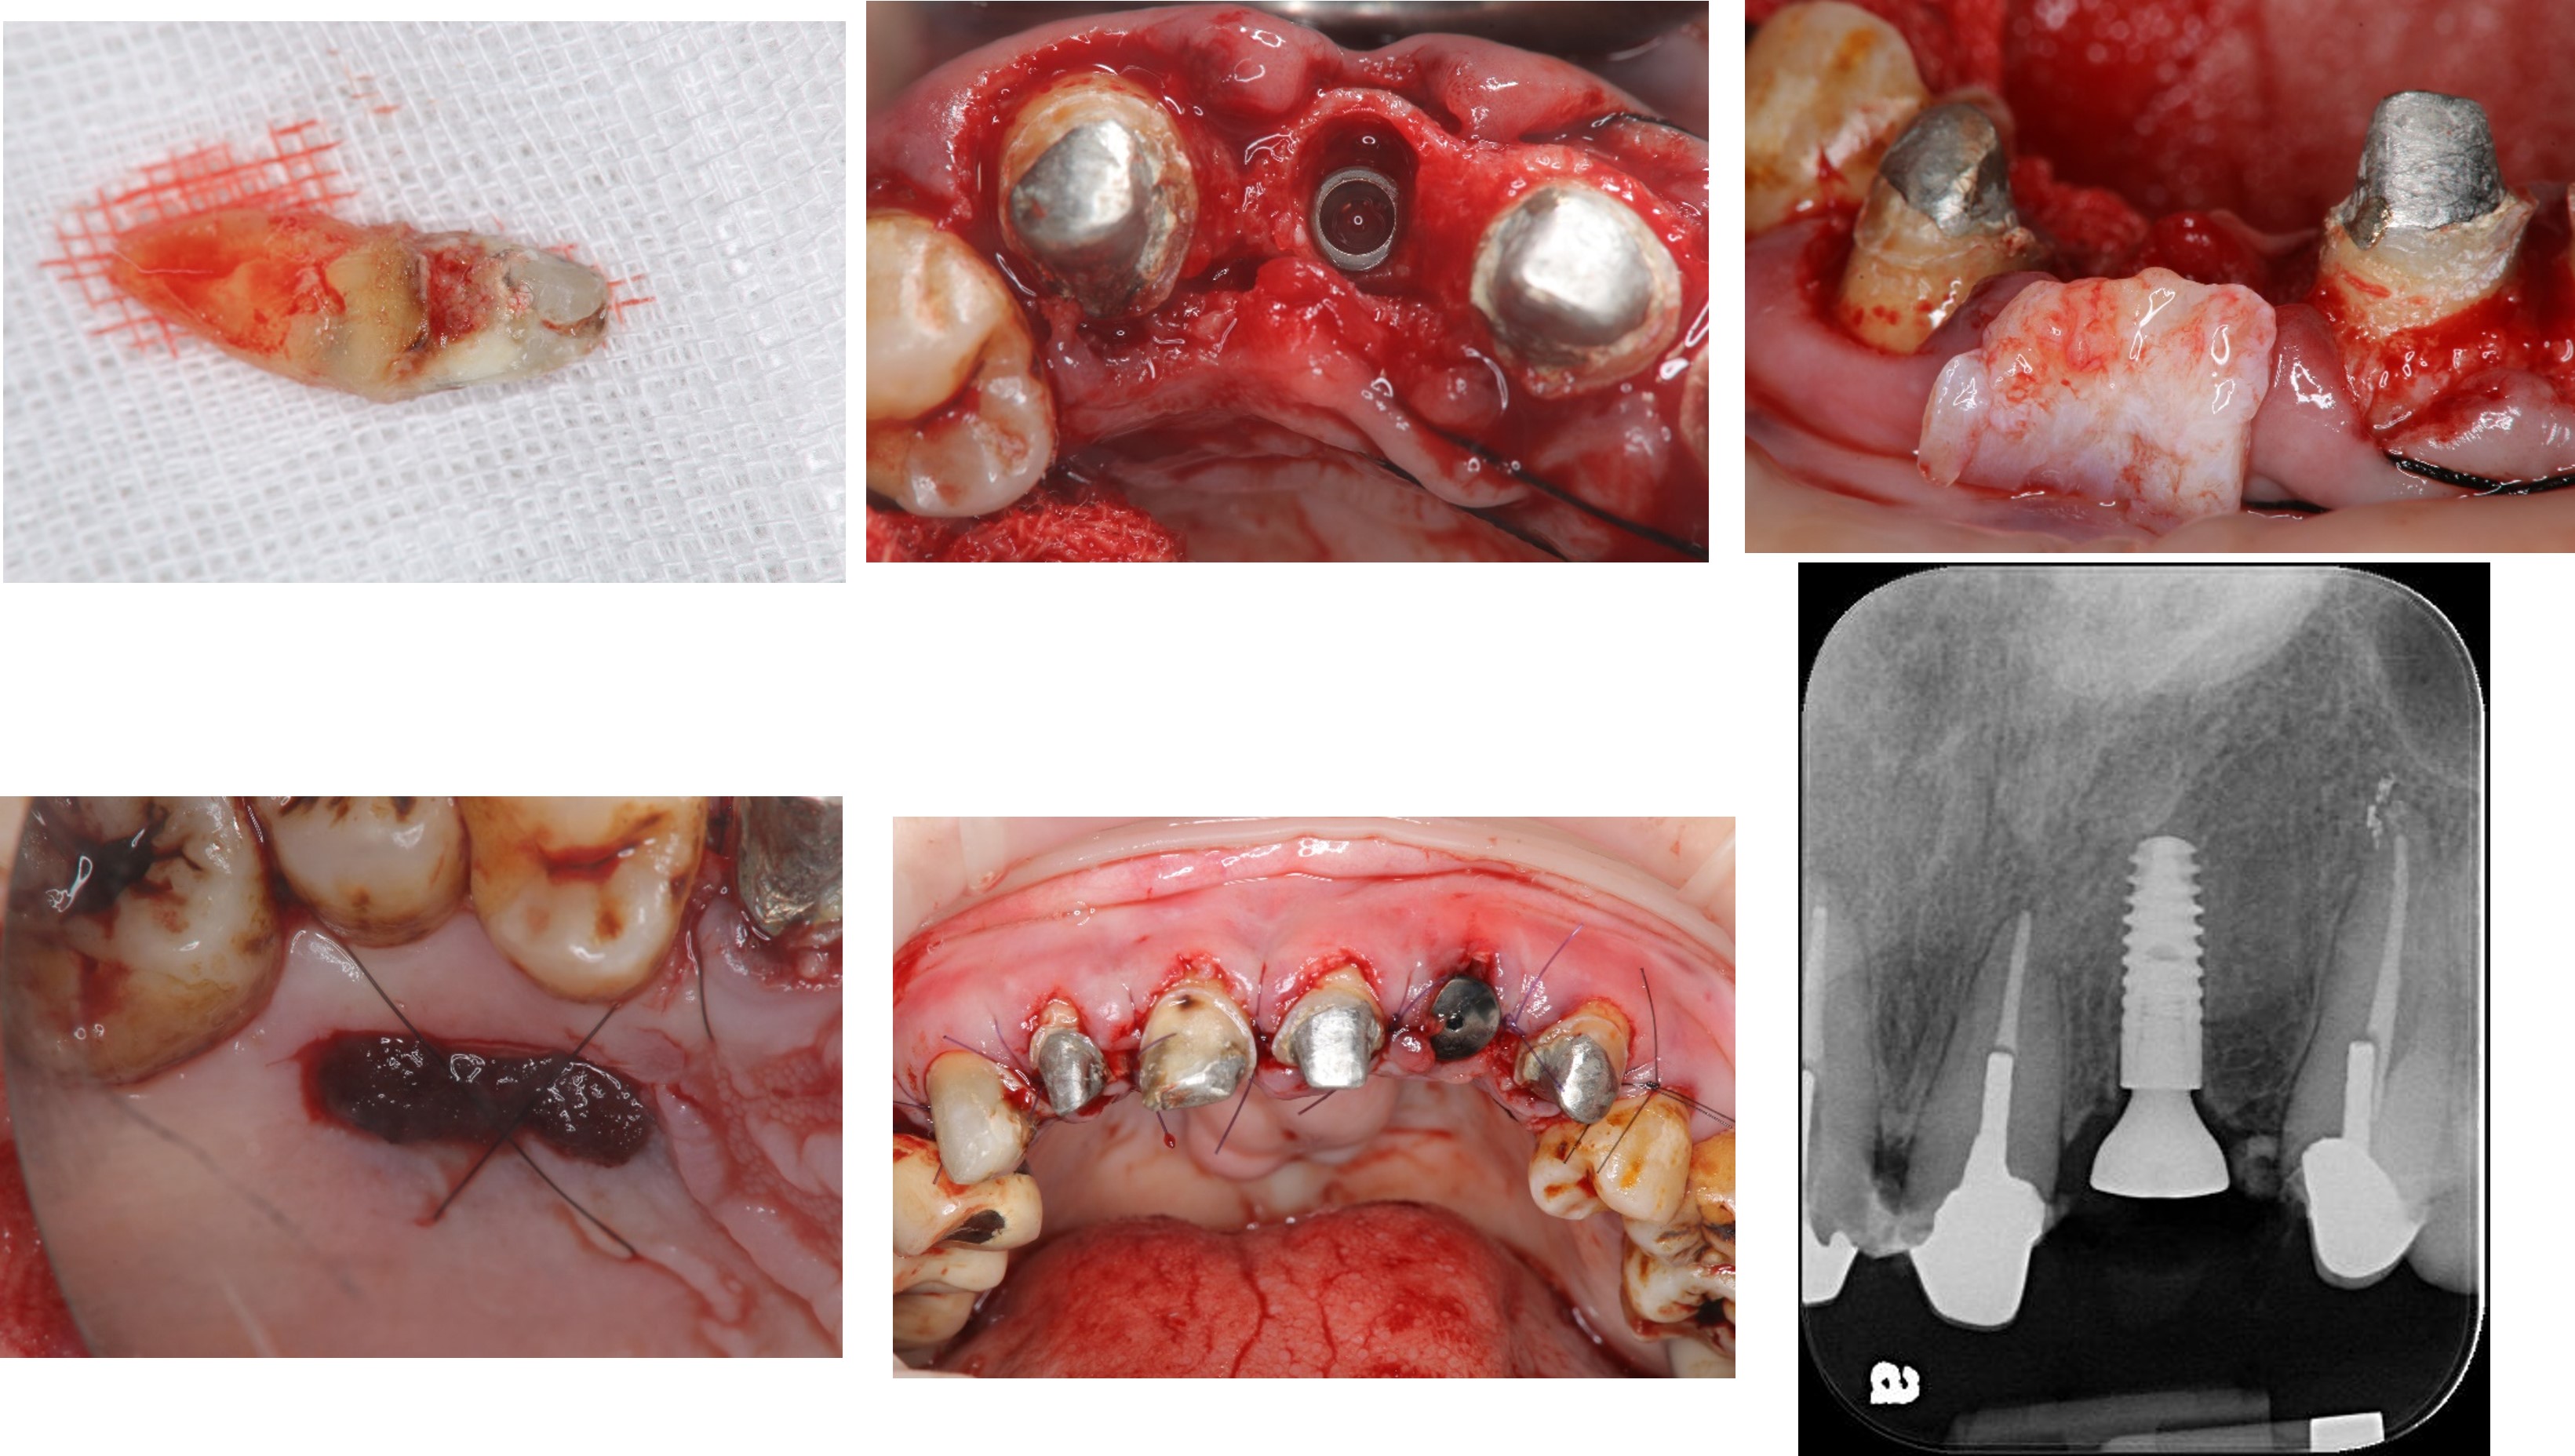

顯微根管治療:#12

顯微根管治療:#11

前牙金屬釘柱復形

拔牙、立即植牙、補骨、補皮

牙齦豐隆度良好